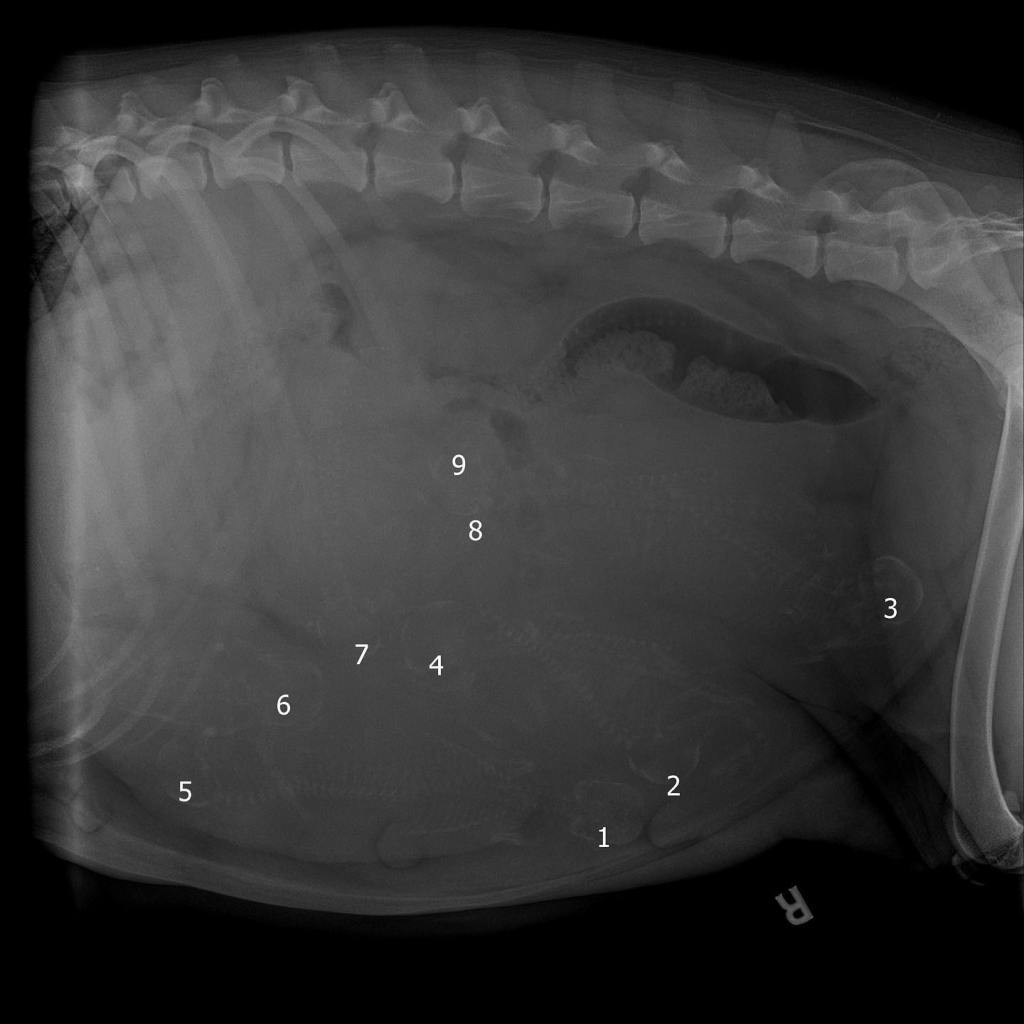

We are excited to announce that Calypso and Voltaire are expecting nine puppies! Calypso is due towards the beginning of September. Please check out our web page LGD Puppies for more in-depth information and our FAQ. We will continually update the situation on both this website and our Facebook page.